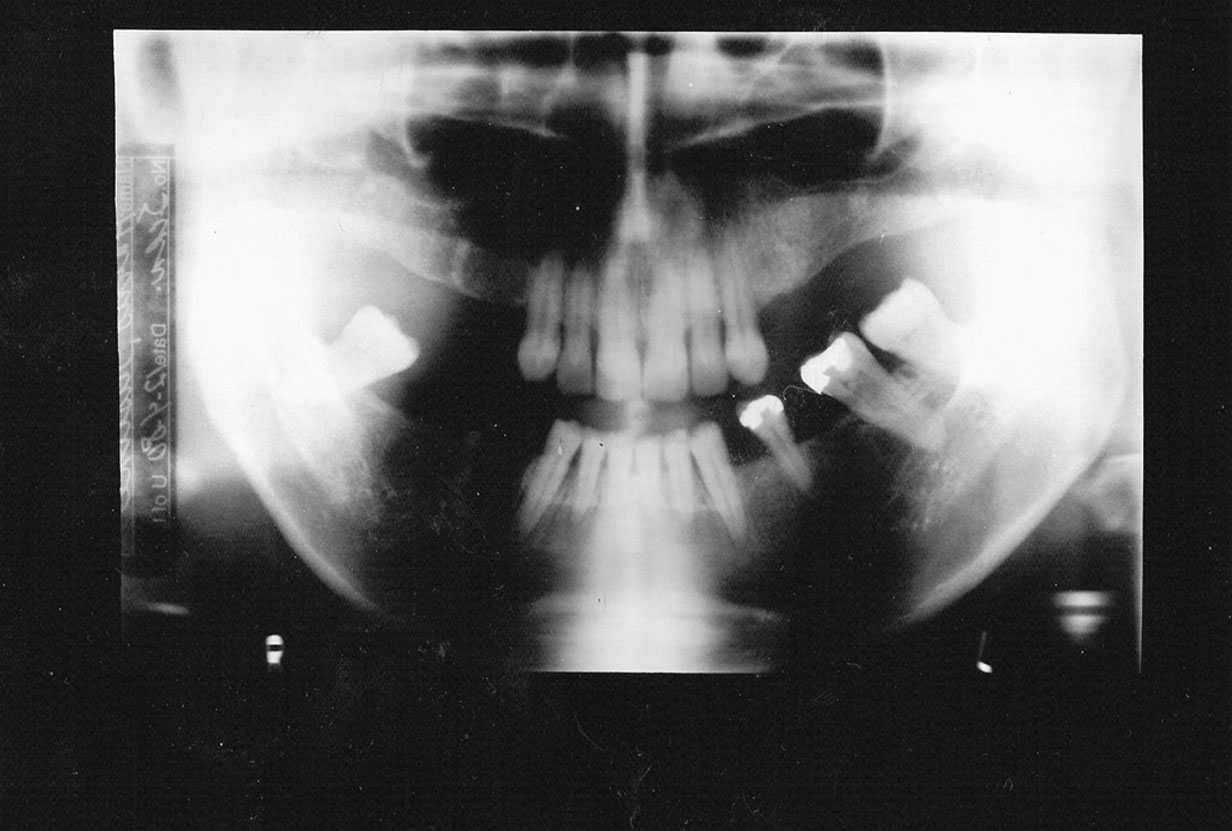

Double Exposure

Description: Double exposures occur when the same film is used for more than one exposure (Figure 1). This can occur if the operator confuses an exposed film with an unexposed film and places the packet into the patient’s mouth as if it were unused. Double exposures can also result from activating the exposure button twice.

Differential Diagnosis: The resulting film is dark because it has technically been overexposed, resulting in confusing, overlapped anatomic images.

Consequences: Retakes are almost always necessary because of the lost detail caused by anatomic superimpositions. Fortunately, double use of a packet usually occurs with the same patient in the chair; but if a previously exposed film from one patient were placed into the mouth of another, the operator would be running the risk of cross-contamination and transmitting disease between patients.

Remedy: After a film packet has been exposed the op­erator should place the film into a lead receptacle. Unexposed films and exposed films should never be kept in the same area.

Figure 1. Double exposure.

Figure 1